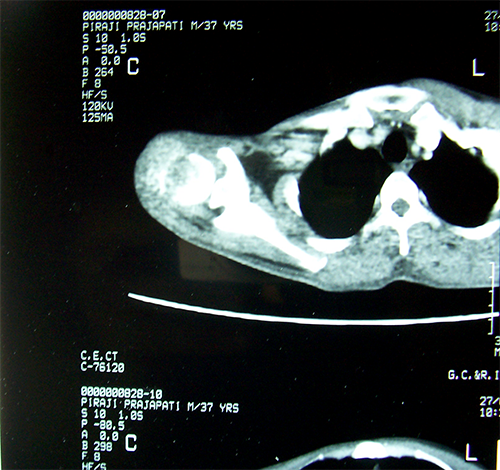

Pre-op CTscan